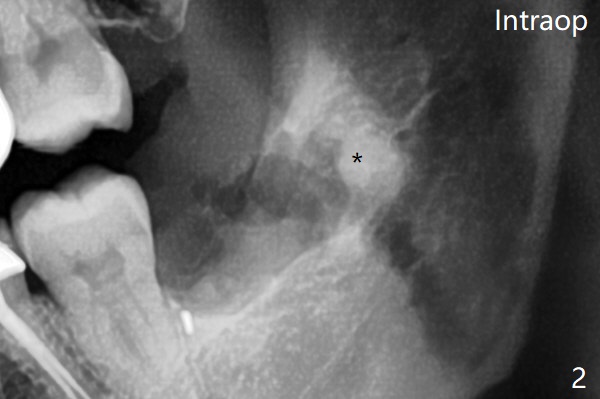

Bone fills the socket 1 year postop (Fig.4). 拔牙顺序: